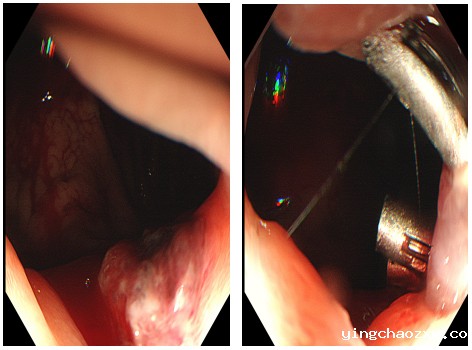

据悉,患者为男性,现年45岁,因“呕血1天”入住新利官网登录西院区肝病脾胃病科。截至入院前已呕吐鲜血8次,总量约600ml,解黑便2次。入院后,又接连解黑便5次, 出血量约900ml。入院前血红蛋白110g/l,入院后复查血红蛋白86g/l,病情危重。如不立即开展内镜下止血治疗,患者极有可能因大量失血导致失血性休克而危及生命。面对患者危重的病情,肝病脾胃病科医疗团队临危不乱,第一时间对患者展开紧急救治,在为患者补充血容量,维持生命体征的同时,紧急联系麻醉科,经过充分评估患者病情,决定为患者实施紧急内镜止血治疗。在麻醉科的通力配合下,紧急内镜止血治疗迅速开展。肝病脾胃病科医疗团队凭借丰富的诊疗经验和精湛的诊疗技术,通过内镜仔细寻找出血点。进境至胃腔见大量鲜血及血凝块,并在贲门食管处发现了一长约8.0cm撕裂的伤口,不断有鲜血渗出。肝病脾胃病科医疗团队迅速对出血部位进行紧急钛夹止血。历经1个小时左右的紧张抢救,患者终于转危为安,现已转入肝病脾胃病科重症病房进行监测和后续治疗。目前,患者在肝病脾胃病科医护人员的精心照料下,生命体征逐渐平稳,身体恢复良好,未出现出血症状,患者及家属对本次治疗非常满意。